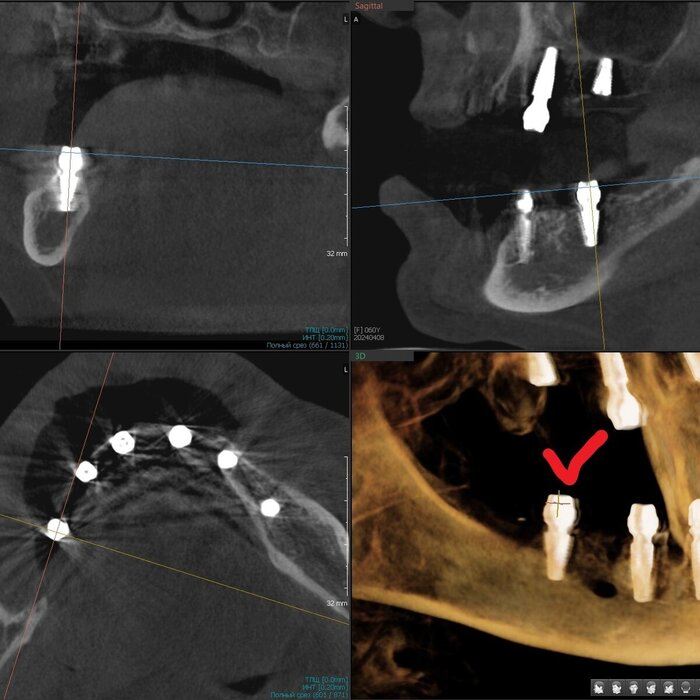

Получилось так, что сверху всего 8 зубов, по 4 с каждой стороны. Чёрная точка (которую вы точно увидите, скос эмали на зубе 1.1) - конструктивные особенности, всё это будет закрыто пломбировочным материалом. Зуб 1.1 - дополнительный имлантат, который потом планируем убрать. Он нужен лишь для усиления, ибо торк полноценный был получен только на одном из остальных 6-ти установленных.

Напоминаю - протезы временные адаптационные

Так же важный момент - верхний протез соприкасается с нижним только в точках полученного торка (их всего 2), остальное "на весу" и жевать не способно.

Рекомендации - мягкая, жидкая пища 4 месяца! Это важно.